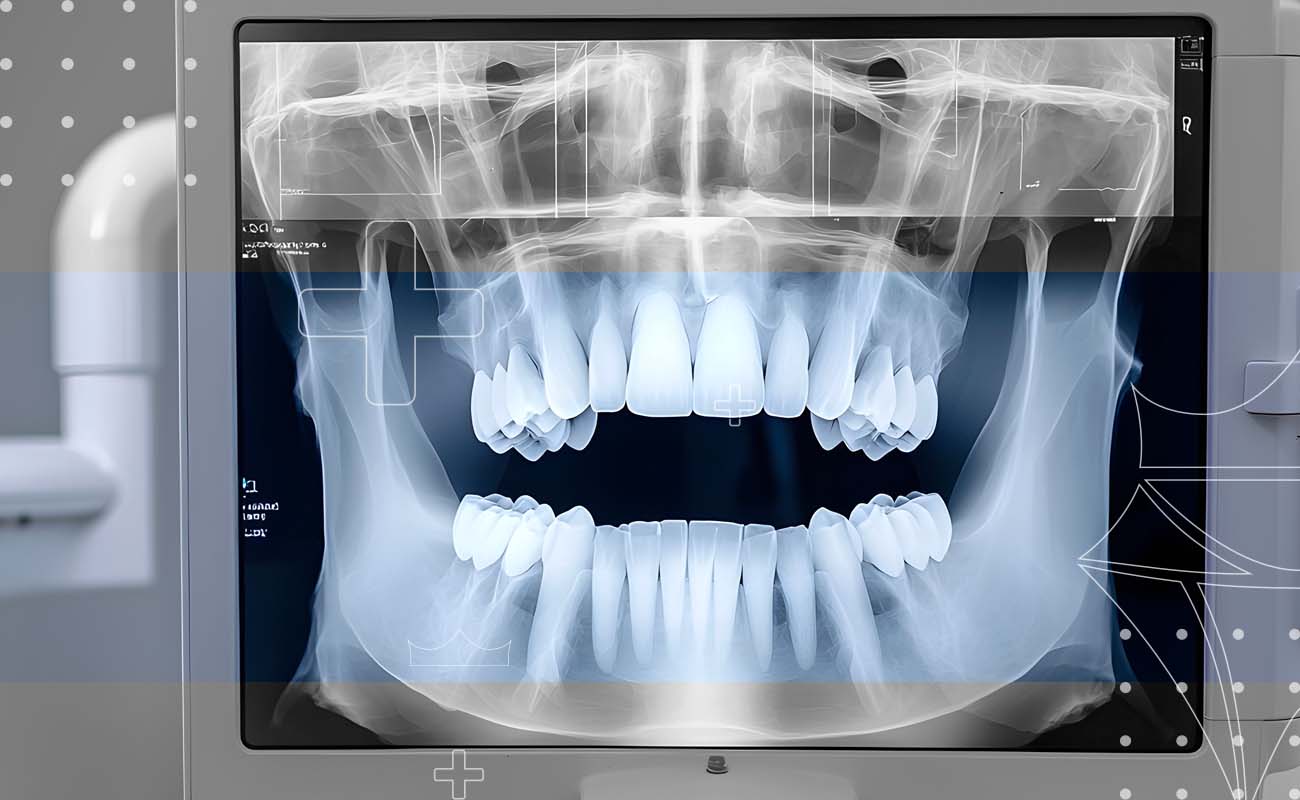

- Detecting Hidden Problems: X-rays can reveal issues like: Cavities between teeth, Infections or abscesses, Bone loss, Impacted teeth and Problems with roots and surrounding bone

- Better Accuracy: The technology provides clearer, more detailed images that can be easily enhanced and magnified, helping our dentists identify issues more easily.

Digital X-rays offer significant advantages that help us provide the best care.

During your visit to our Dubai clinic, our expert team will examine your teeth, gums, and mouth using advanced digital X-rays. This low-radiation technology gives us a clear view of your oral health, helping spot issues like cavities or bone loss early—before they become serious.

- is a diagnostic tool that captures detailed images of your teeth and jawbone, revealing things that aren't visible during a standard exam.